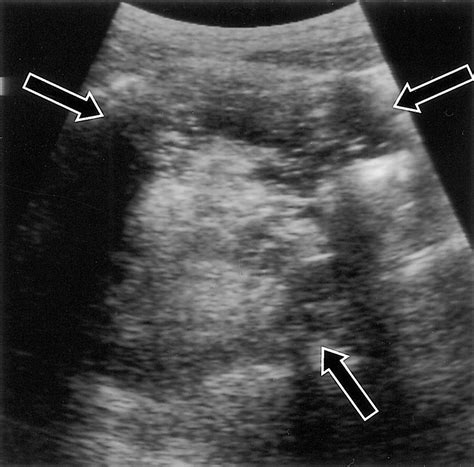

When doctors request scans, they are looking for specific visual identifiers. Imaging techniques such as CT scans, MRIs, and ultrasounds are standard. In these images, a teratoma often appears as a complex mass with both cystic (fluid-filled) and solid components. The presence of fat, calcifications (which look like bone or teeth on an X-ray), and soft tissue elements are hallmark signs that radiologists use to identify the growth.

While looking for Teratoma Cancer Pictures online, patients may see varying representations, but it is important to note that internal clinical imaging (like an MRI) looks significantly different from external surgical photography. Radiology provides the map for surgical intervention, helping surgeons understand the proximity of the tumor to vital organs.